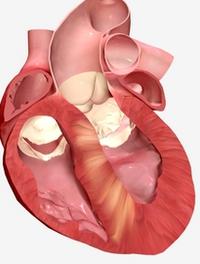

Les inhibiteurs de la myosine cardiaque ont été récemment proposés en traitement de la cardiomyopathie hypertrophique (CMH) qui reste [...]

Les « gastrointestinal stromal tumors » (GIST) sont les plus fréquentes des tumeurs mésenchymateuses du tractus digestif, mais ne représentent [...]